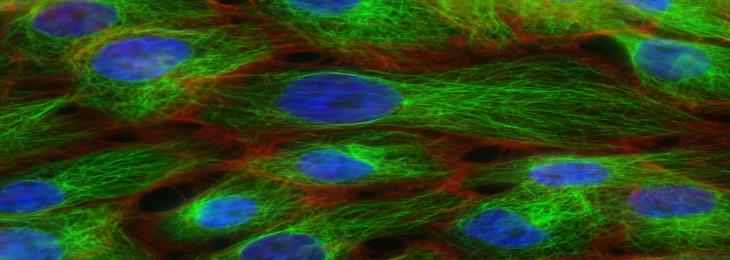

Researchers discovered genetically engineered cells that automatically release a biological drug in response to inflammation. A ne...